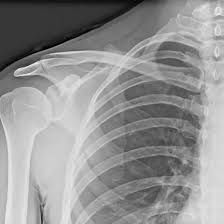

X-ray of Right Shoulder Joint AP/Lateral Views

An X-ray of the Right Shoulder Joint AP/Lateral is a diagnostic imaging procedure that captures detailed images of the shoulder joint from two perspectives: Anteroposterior (AP) and Lateral views. The AP view shows a front-to-back image, whereas the Lateral view shows a side image, allowing for a thorough examination of the shoulder’s bony structures. This imaging approach is useful for identifying diseases such as fractures, dislocations, arthritis, infections, and other anomalies of the shoulder joint. It is a safe, quick, and non-invasive procedure commonly used to evaluate shoulder pain, injury, or dysfunction.

An X-ray of the right shoulder joint AP/Lateral views can detect fractures, dislocations, arthritis, and bone abnormalities. It helps assess bone alignment, joint space, and signs of injury or degeneration.